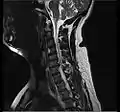

- Magnetic resonance imaging (MRI) without contrast is a diagnostic test that produces three-dimensional images of body structures using powerful magnets and computer technology. It can show the spinal cord, nerve roots, and surrounding areas, as well as enlargement, degeneration, and tumors. It shows soft tissues better than CAT scans. An MRI performed with a high magnetic field strength usually provides the most conclusive evidence for diagnosis of a disc herniation. T2-weighted images allow for clear visualization of protruded disc material in the spinal canal.

MRI scan of cervical disc herniation between C5 and C6 vertebrae.

MRI scan of cervical disc herniation between C6 and C7 vertebrae

Cervical disc herniations occur in the neck, most often between the fifth and sixth (C5–6) and the sixth and seventh (C6–7) cervical vertebral bodies. There is an increased susceptibility amongst older (60+) patients to herniations higher in the neck, especially at C3–4.[21] Symptoms of cervical herniations may be felt in the back of the skull, the neck, shoulder girdle, scapula, arm, and hand.[22] The nerves of the cervical plexus and brachial plexus can be affected.[23]